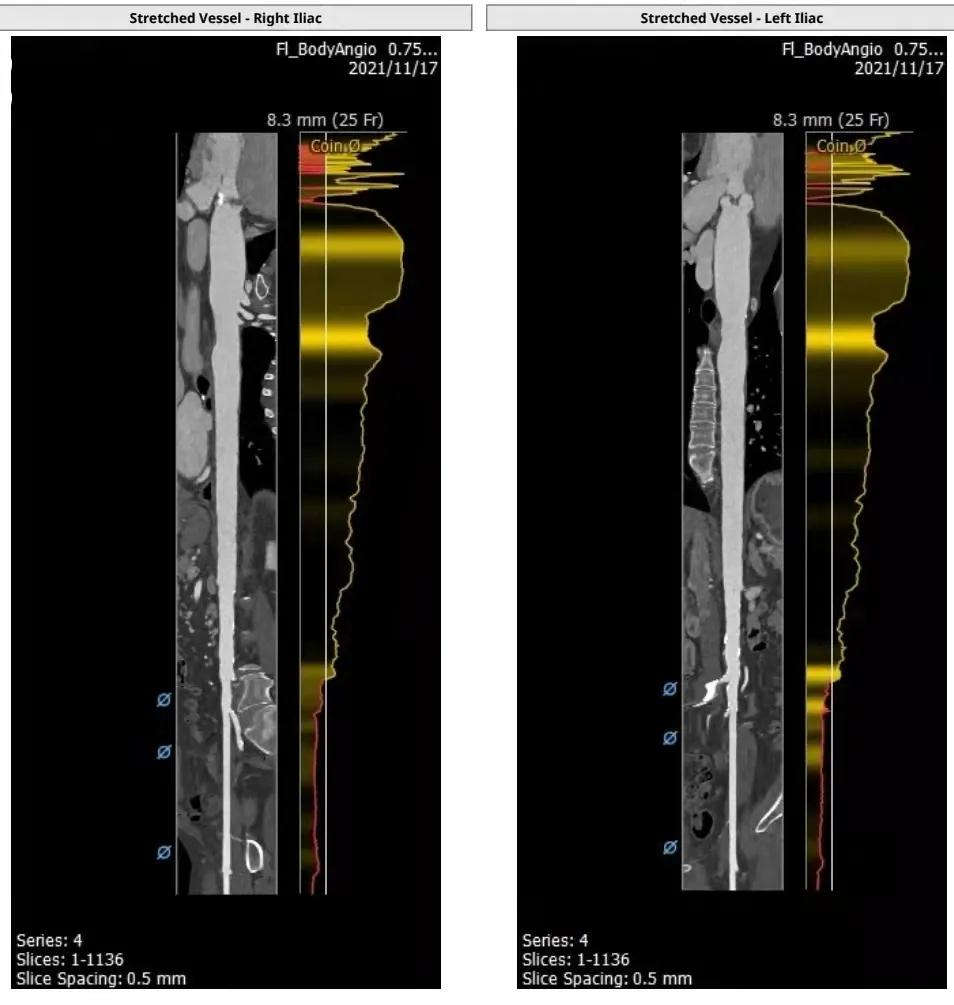

血管入路评估:

综合评估:瓣叶以增厚为主,冠脉高度可,双下肢内径可,术者决定采用20mm球囊预扩,选择植入Silara A-23mm瓣膜。